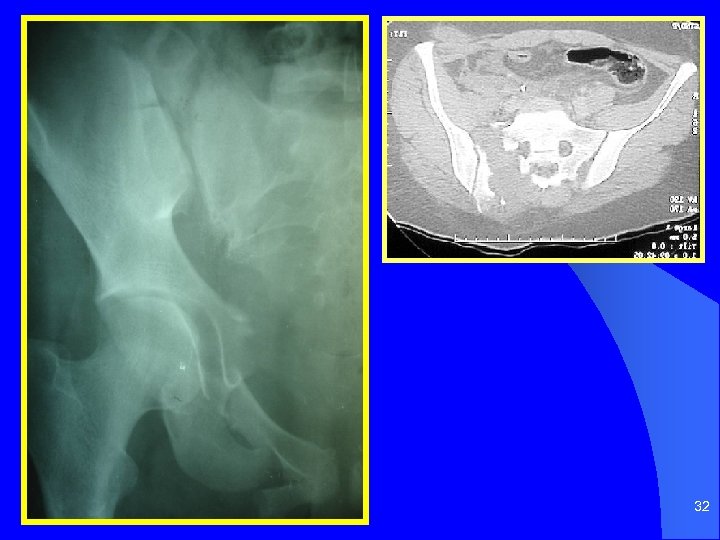

32